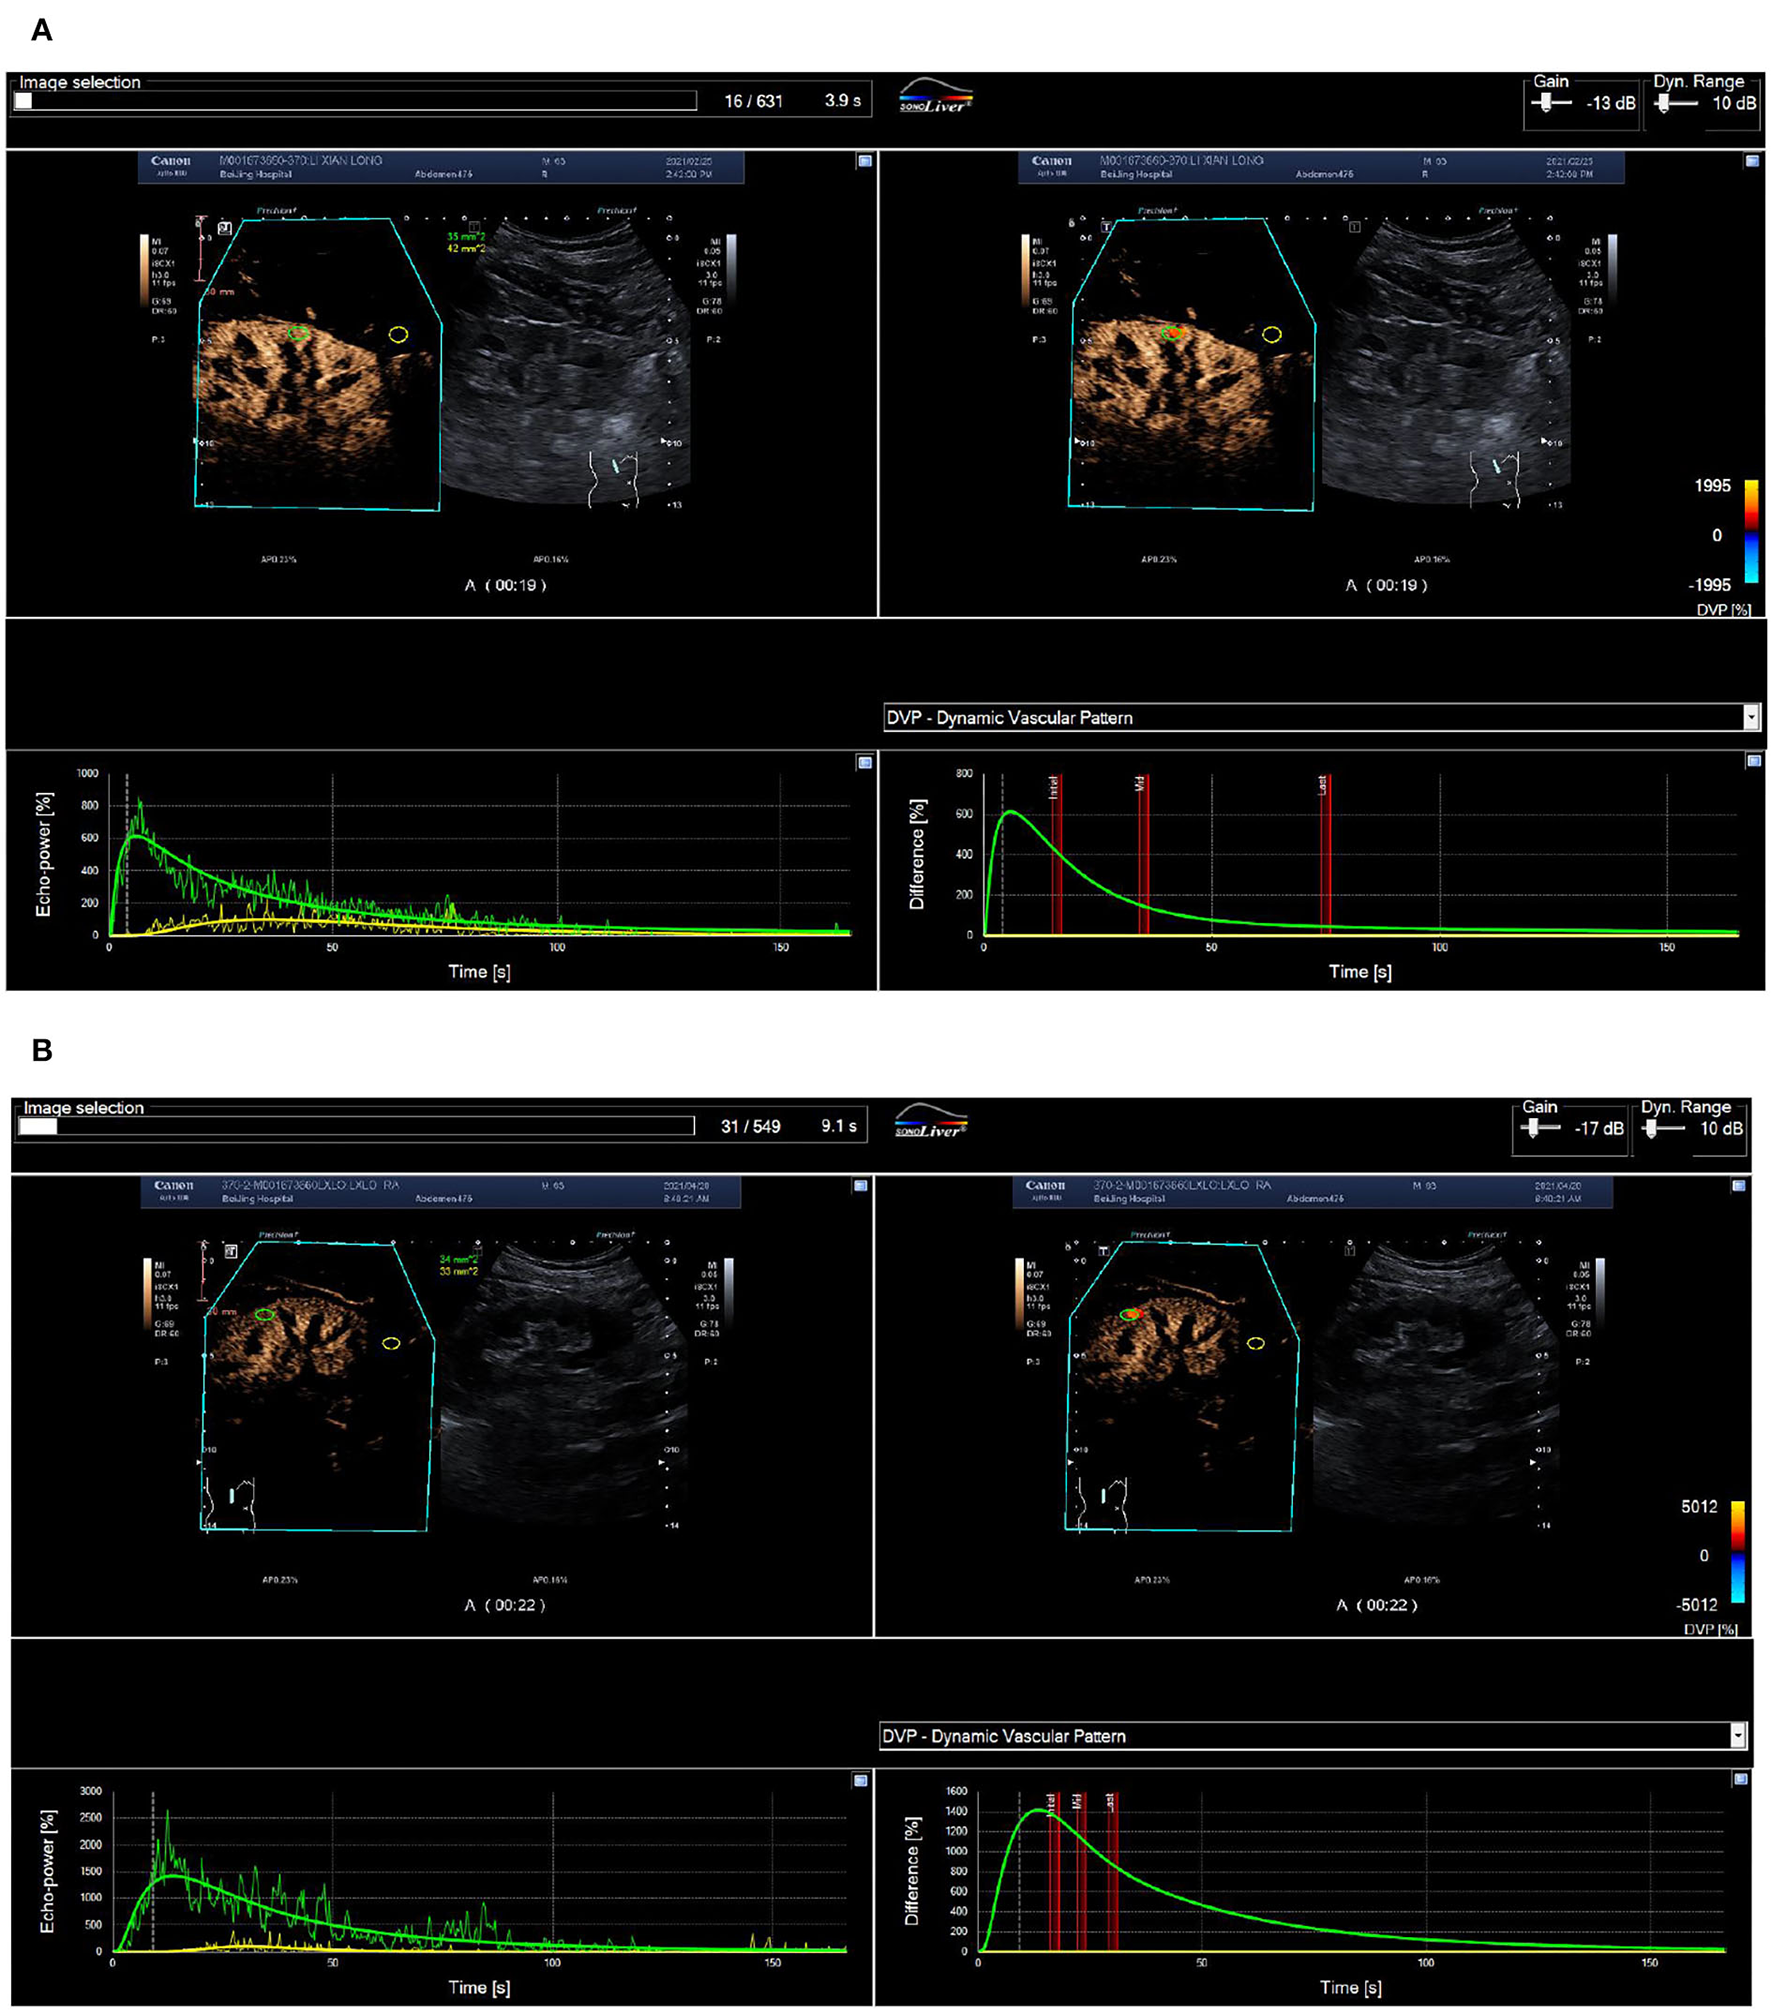

After stent implantation, the BP nonresponse group was associated with significantly reduced RT (P < 0.05), but other CBP parameters (IMAX, TTP, mTT, AUC1, and AUC2) did not change significantly (P > 0.05) (Figure 2). In the BP response group, IMAX, AUC1, and AUC2 were significantly increased, while the RT and mTT were significantly shortened (P < 0.05), and TTP was significantly prolonged compared with pre-operation (P < 0.05) (Table 2).

Figure 2

Routine ultrasound and CEUS images of a 65-year-old man with 70% right renal ostial stenosis. (A) Color Doppler flow (left), Doppler frequency spectrum (middle), and CEUS (right) images of the long axis section of right renal artery before PTRAS. (B) After stent implantation, renal artery blood flow images (left) and the peak systolic velocity (middle) of stenosis were corrected, and contrast beam filling (right) displayed normal. RA, renal artery; AO, abdominal aorta. (A) Pre-operative cortical blood perfusion, IMAX (%): 855.1, RT (s): 7.7, TTP (s): 8.3, mTT (s): 42.5, AUC1: 47.5, AUC2: 308.4; (B) Post-operative cortical blood perfusion, IMAX (%): 725.3, RT (s): 6.7, TTP (s): 7.3, mTT (s): 27.9, AUC1: 34.6, AUC2: 194.4. Changes in cortical blood perfusion before (A) and after (B) stent implantation of a 57-year-old woman with severe stenosis of the right renal artery in the BP nonresponse group.

After stent implantation, compared with the BP nonresponse group, the CBP of the BP response group was significantly different, manifested as a significant increase in IMAX, AUC1, and AUC2, and an increase in RT, mTT, and TTP (P < 0.05) (Figures 2, 3).

Figure 3

ROC curve of renal blood perfusion parameters for predicting poor prognosis. (A) Pre-operative cortical blood perfusion, IMAX (%): 614.7, RT (s): 5.8, TTP (s): 5.9, mTT (s): 78.4, AUC1: 26.0, AUC2: 251.6; (B) Post-operative cortical blood perfusion, IMAX (%): 1422.4, RT (s): 12.2, TTP (s): 13.6, mTT (s): 45.6, AUC1: 119.4, AUC2: 632.6. Changes in cortical blood perfusion before (A) and after (B) stent implantation of a 53-year-old man with severe stenosis of the left renal artery in the BP response group.